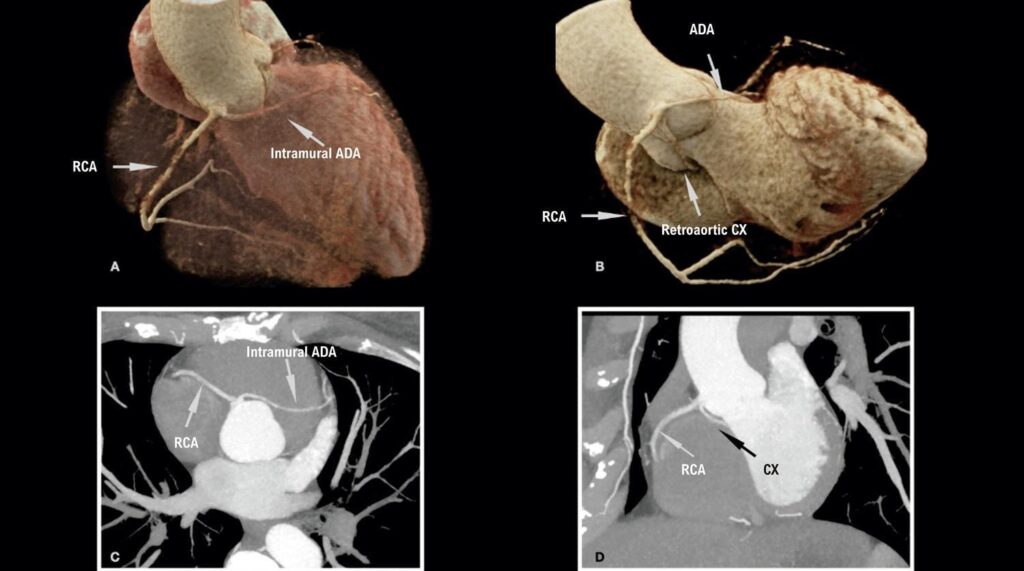

Rare Presentation of an Anatomical Congenital Anomaly of the Coronary Arteries on Computed Tomography Angiography

Anomalous origin of the coronary arteries represents a heterogeneous group of alterations in the origin and course of these vessels, ranging from the most common, asymptomatic and low risk, to the rarest and highest risk, which may eventually be symptomatic or have sudden death as their first manifestation., Their prevalence corresponds to 1.3% of patients undergoing coronary angiography, but this number may be higher depending on the diagnostic method and the population selected, representing the second leading cause of sudden death in young athletes, behind only hypertrophic cardiomyopathy.,

Within this group, coronary anomalies with a single ostium are present in a smaller proportion of the population, approximately 0.004% to 0.098%. They are most often asymptomatic, but they may manifest with chest pain, dyspnea, palpitation, myocardial infarction, and sudden death., The presentation of this anomaly has worse prognosis in the presence of an interarterial vessel course (between the aorta and pulmonary trunk), an acute angle of origin, and atherosclerotic plaque; the latter change has a higher incidence in anomalous vessels on account of the greater stress on the arterial wall., In addition to presenting in isolation, they may also be associated with other alterations such as cardiac fistulas or a bicuspid aortic valve.